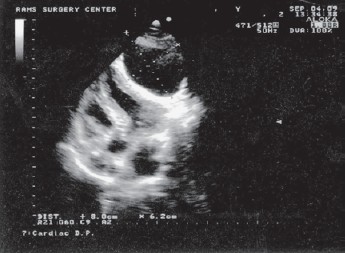

При трансторакальной ЭхоКГ отмечены увеличение правых отделов сердца и овальной формы образование размером 4,4х3,2 см, содержащее жидкость и тонкую перемычку, видимую при получении изображения в реальном времени и исходящее из правой части МЖП, занимающее большую часть полости правого желудочка (рис. 3).

Рисунок 3.Двухмерная ЭхоКГ пациентки Б., 9 лет.

Эхинококковая киста в полости правого желудочка, исходящая из МЖП. 1 - полость правого желудочка.